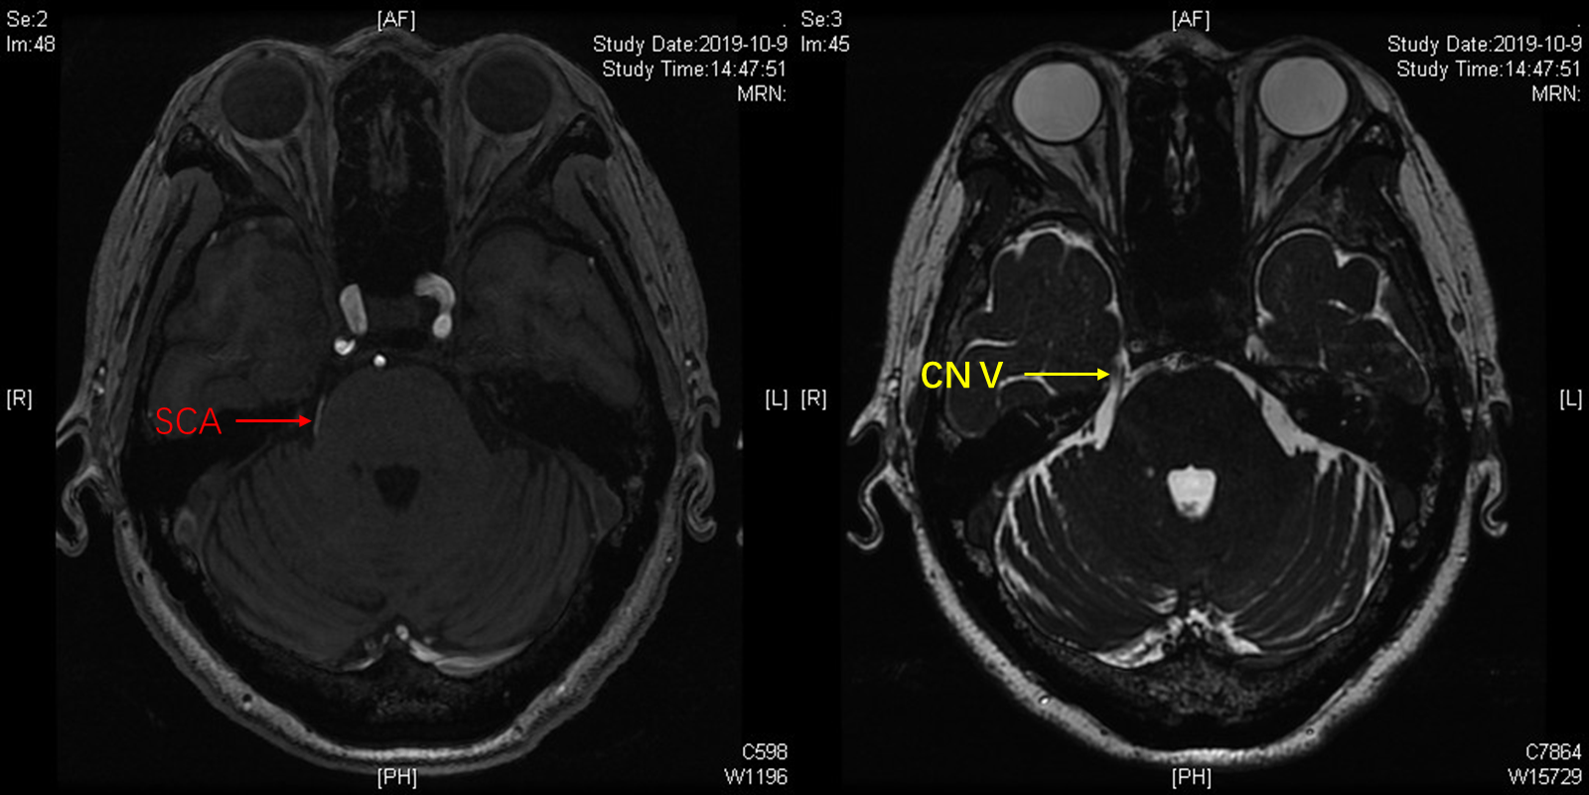

MRTA可见,小脑上动脉与右侧三叉神经关系密切,且与之紧贴,脑池空间(白色)狭小,三叉神经与岩骨距离近。

术中充分释放脑脊液,从面听神经与岩静脉之间的间隙观察三叉神经。

神经内镜抵近观察(岩静脉的阻挡迎刃而解,内镜的优势体现),岩骨、SCA与三叉神经紧贴,减压空间较小。